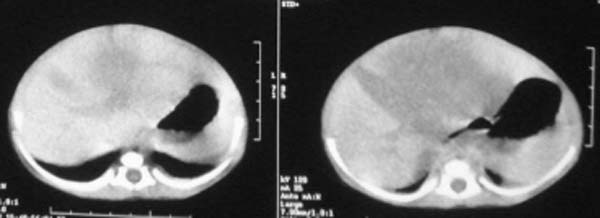

这个病例定位诊断:1、可以肯定肿块不在肝脏。2、肿块在腹膜后,因为肠管向前侧方推移,肾脏明显向后推挤,腹主动脉及下腔静脉被肿块包绕。

我的意见是-----定位诊断是“1、可以肯定肿块不在肝脏。2、肿块在腹膜后,因为肠管向前侧方推移,肾脏明显向后推挤,腹主动脉及下腔静脉被肿块包绕。”

右中下腹部囊实性密度影,内有小细条状钙化影,胃及腹部肠管受压向左移位,肾脏受压向后移位,腹主动脉及下腔静脉包饶。考虑腹膜后畸胎瘤可能性大。